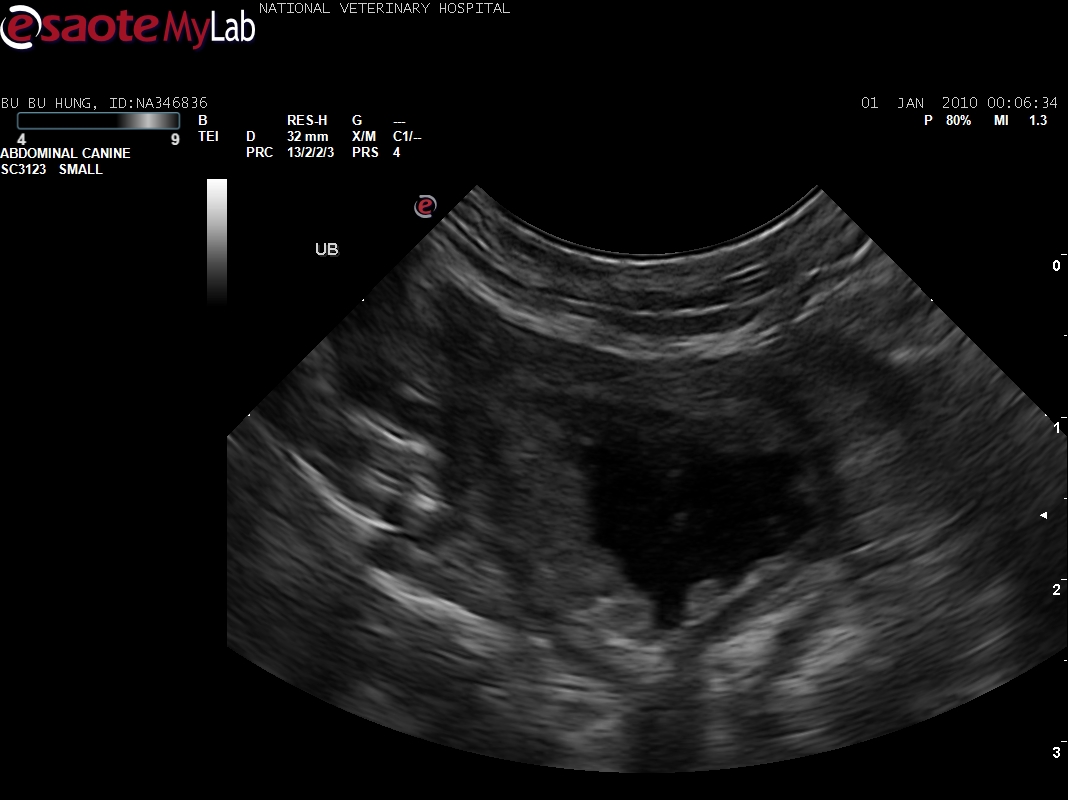

16.2.jpg